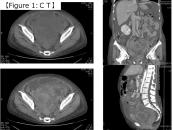

第36回日本臨床細胞学会九州連合会学会(大分)スライドカンファレンス症例4

種別:体腔液

出題:宮崎県立宮崎病院 病理診断科 丸塚 浩助

| 年齢 | 50代後半 | 性別 | 女性 |

|---|---|---|---|

| 採取部位 | 腹水 | 採取方法 | 穿刺 |

| 検体処理法 | 塗抹及びLBC |

臨床所見

<既往歴>

特記なし

<現病歴>

2ヶ月前頃より腹部膨満・下腿浮腫を自覚し、当院産婦人科に紹介受診。MRIにて著明な腹水と骨盤腔内を占める腫瘤が認められ、癌性腹水を伴う卵巣癌との臨床診断で腹水穿刺細胞診が行われた。

化学療法後開腹手術を行ったが、びまん性腹膜播種を認め、腫瘍切除のみ行われた。腫瘍はS状結腸腸間膜に存在し、卵巣・子宮は正常外観であった。

| 正解 | 5.炎症性筋線維芽細胞肉腫 |

▼選択肢及び投票結果

| 1.卵巣漿液性腺癌 | 5件 | (7.8%) | |

| 2.腹膜中皮腫 | 3件 | (4.7%) | |

| 3.消化管間質腫瘍 | 1件 | (1.6%) | |

| 4.未分化大細胞リンパ腫 | 42件 | (65.6%) | |

| 5.炎症性筋線維芽細胞肉腫 | 13件 | (20.3%) | |

| 投票総数 | 64件 | (100%) |